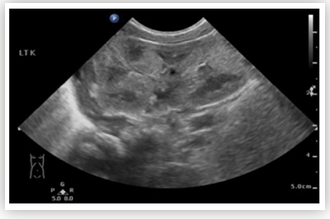

Case Report

Ovarian Juvenile Granulosa Cell Tumor in Childhood: The Importance of Early Diagnosis. Case Report

Fatma Chebab, Aida Daib, Rabiaa Ben Abdallah, Malek Boughdir, Sameh Tlili and Nejib Kaabar.